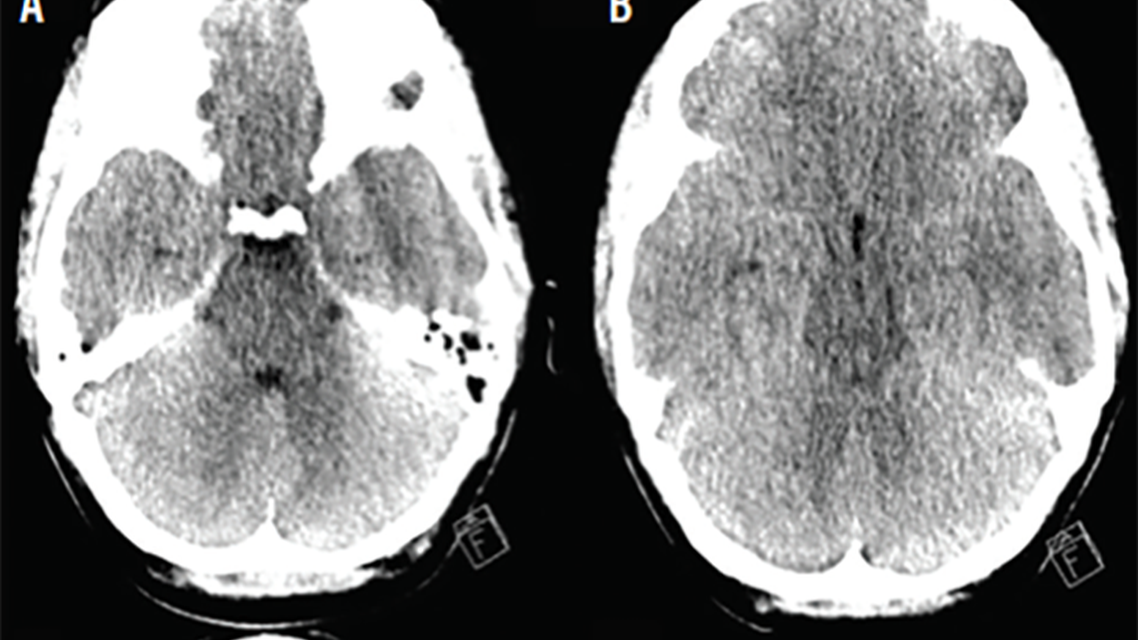

Laboratory studies revealed serum sodium level of 116 mEq/L, and a urine drug screen was positive for amphetamines and benzodiazepines. Head CT (Figure 1) demonstrated diffuse cerebral edema with effacement of the quadrigeminal and basal cisterns. To work up the etiology of Ms BR’s hyponatremia, urinalysis was performed, and results were urine sodium 34 mEq/L, urine specific gravity 1.003, and urine osmolality 127 mOsm/kg.